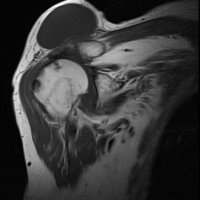

The geyser sign is a subcutaneous pseudotumor above the acromioclavicular joint, also known as AC joint cyst. The geyser sign is an infrequently encountered imaging sign that was originally described on conventional fluoroscopy-guided shoulder arthrography. The first case report of these cysts occuring in association with rotator cuff tears was made by Dr. Edward Craig in 1984, and again in 1986. The sign derives its name from its geyser-like appearance.

On physical examination, an AC joint cyst is a palpable fluid-filled mass. MRI scanning or a shoulder arthrogram should be obtained to evaluate the shoulder. Unenhanced MRI scans showing a large rotator cuff tear, a degenerated AC joint, and a large subcutaneous cyst adjacent to the AC joint is virtually patognomonic for the disease. Contrast administration on MR arthrogram will show the synovial fluid or intra-articular contrast extravasates from the glenohumeral joint into the subacromial bursa, into the AC joint, and then into an overlying cystic mass when a full-thickness rotator cuff tear is present, resembling a geyser spouting upwards.